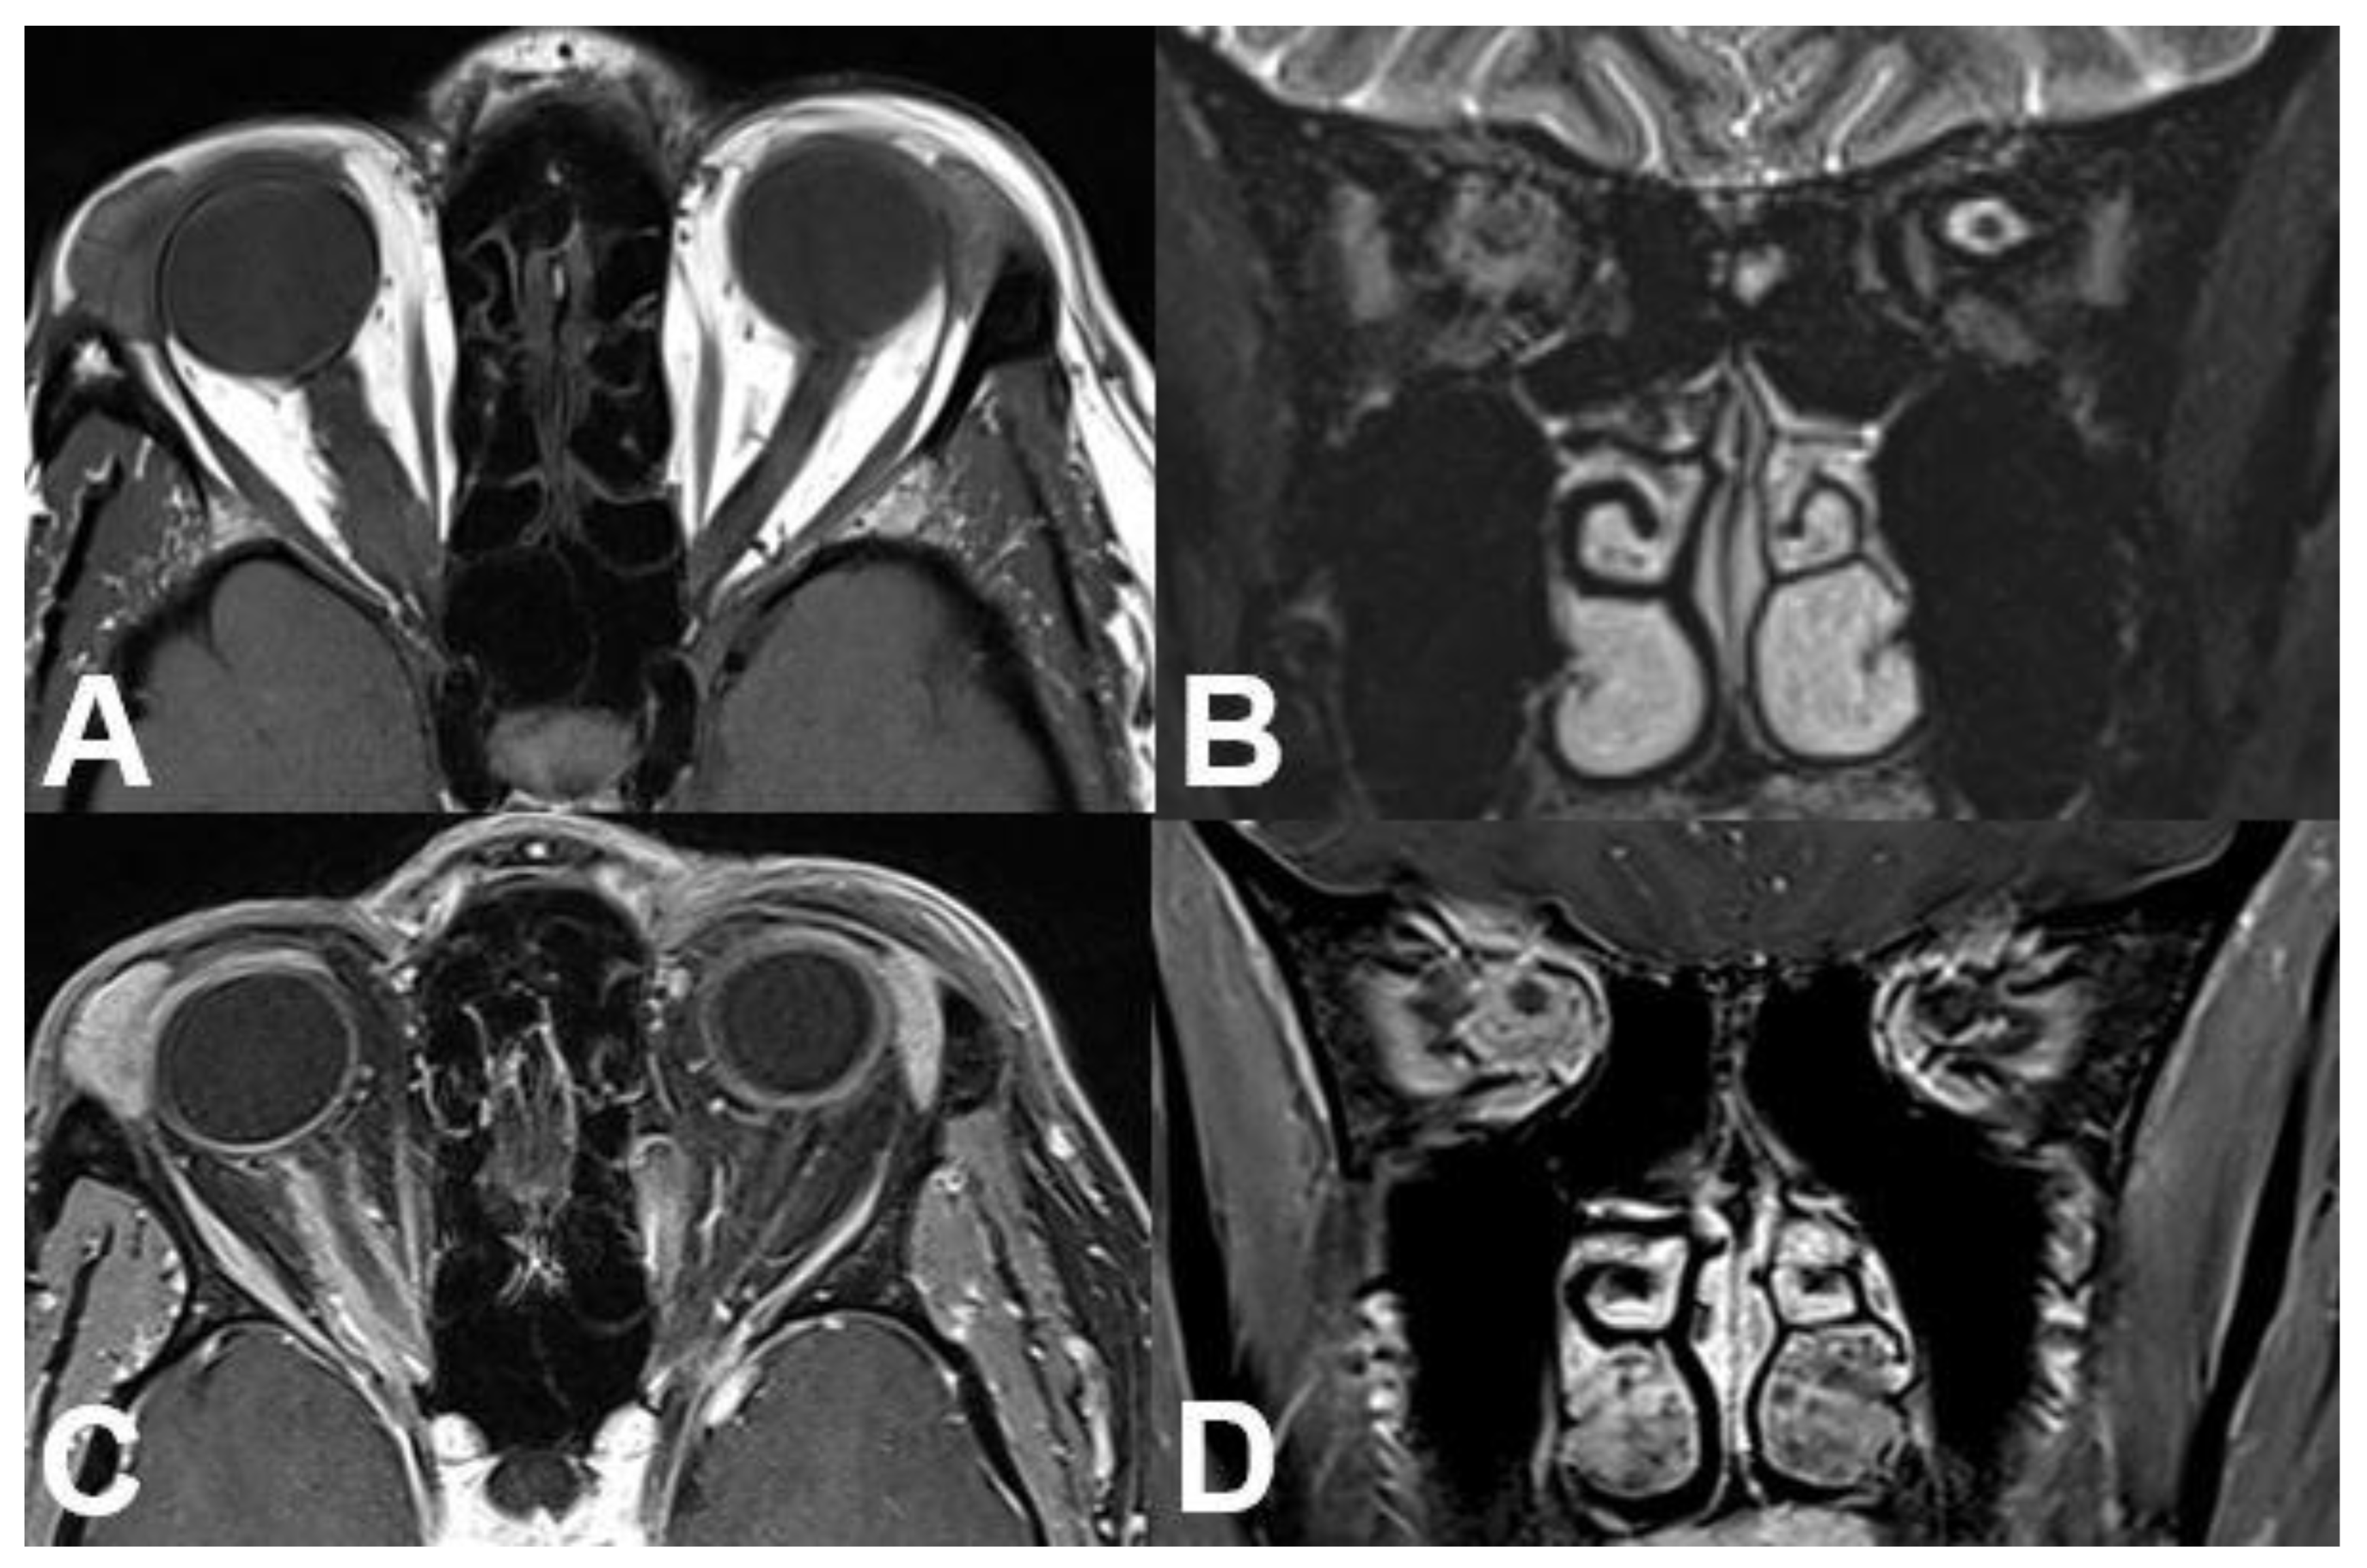

3.1.1. Retinoblastoma